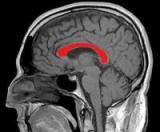

Мозолистое тело мозга — это толстые группы нервных волокон, соединяющие две половинки мозга друг с другом и обеспечивающие возможность быстрого обмена информацией между левым и правым полушариями. Они играют важную...